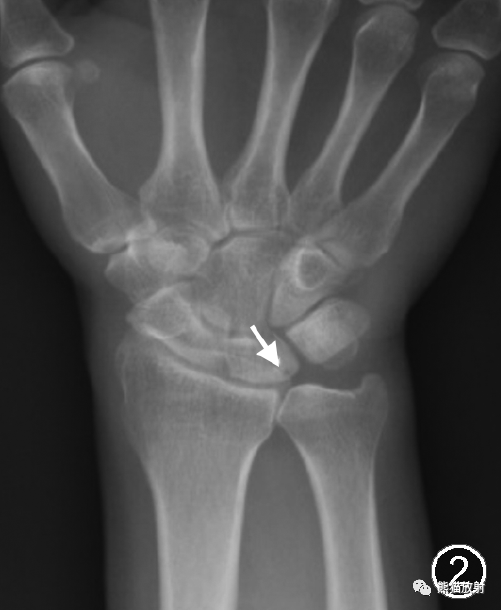

标准后前位(肩关节外展90°、肘关节屈曲90°、腕关节中立位)X线摄片的典型表现包括尺骨正向变异,偶尔可见尺骨中性变异或尺骨负向变异,以及导致尺骨相对过长或桡骨远端背倾程度增加的其他因素,例如桡骨远端骨折的畸形愈合(图1);月骨近端尺侧面、三角骨近端桡侧面及尺骨头关节面硬化和软骨下囊变(图1,2)。

图2 尺骨正向变异所致尺骨撞击综合征。男,48岁,右腕关节疼痛。腕关节X线正位片示尺骨正向变异,月骨近端尺侧面骨质硬化囊变(↑)